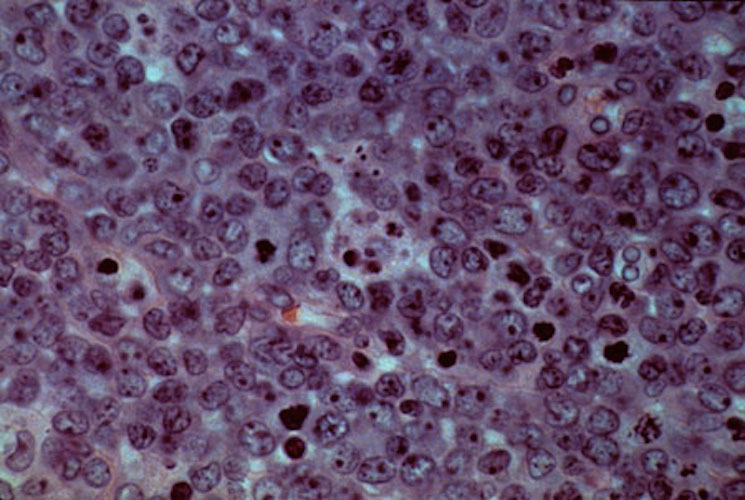

STAT+: Allogene Therapeutics’ CAR-T treatment eliminates residual cancer cells in B-cell lymphoma patients